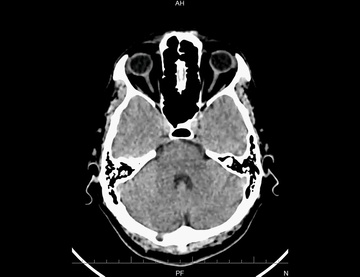

КТ головного мозга с контрастом / МСКТ головного мозга с контрастированием)

КТ головного мозга с контрастом – это диагностический метод, позволяющий на раннем этапе обнаружить патологии, аномалии развития и последствия травм головы. Он является дальнейшим развитием технологии...